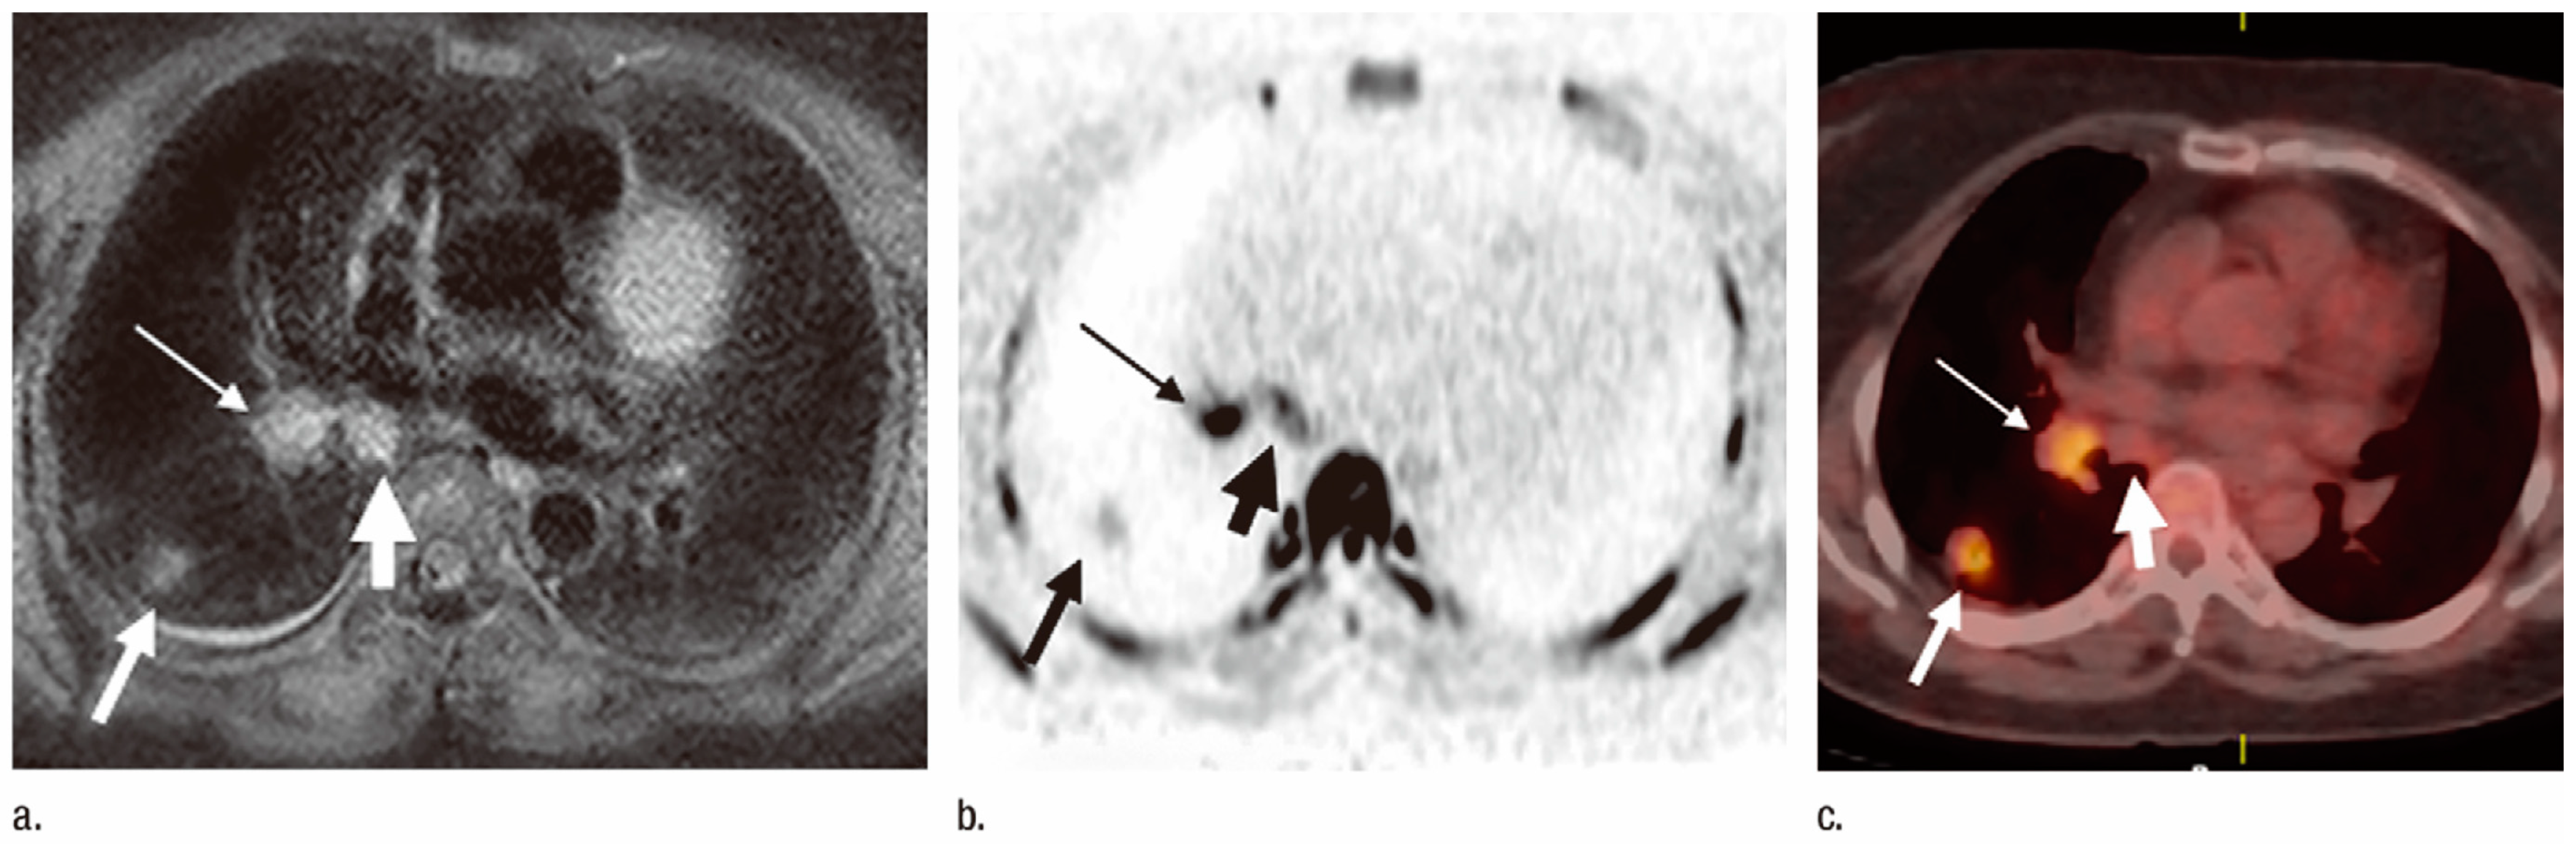

3.2. N-Factor Assessment

3.3. M-Factor Assessment